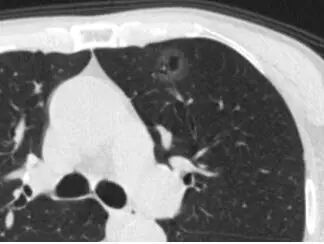

当逐渐长大进展,纯 GGO 的实性成分增加,成为「混合性GGO」。有时,还会出现分叶、毛刺、空泡,胸膜凹陷,血管密集等改变,这时多数已经是恶性了,为浸润性腺癌——可侵犯血管、肺内或全身转移。